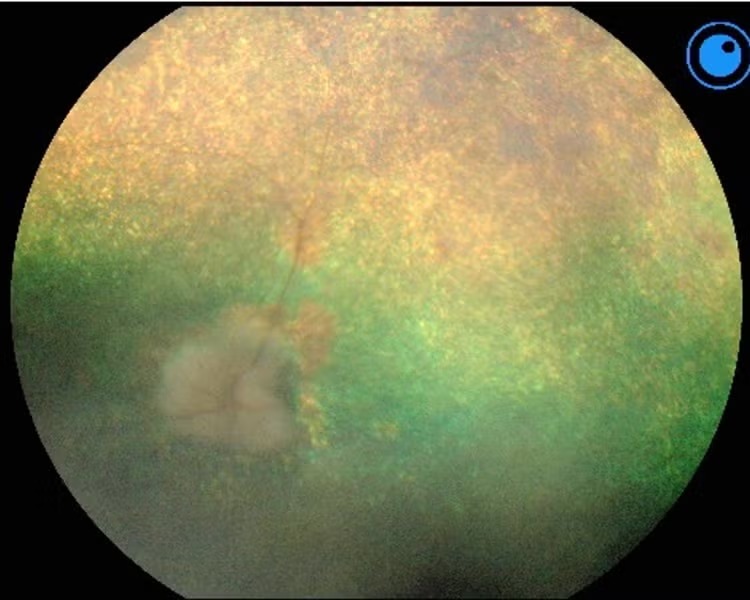

kép: PRA-val érintett kutya szemfeneke (fundusfelvétel)

A PRA diagnosztizálásához alapos szemészeti vizsgálat szükséges (pupillatágítással). A szemész állatorvos megvizsgálja a retina állapotát, aminek eltérése sokszor már az első tünetek megjelenése előtt látható. A diagnosztikai további lehetőségei között szerepelhet: